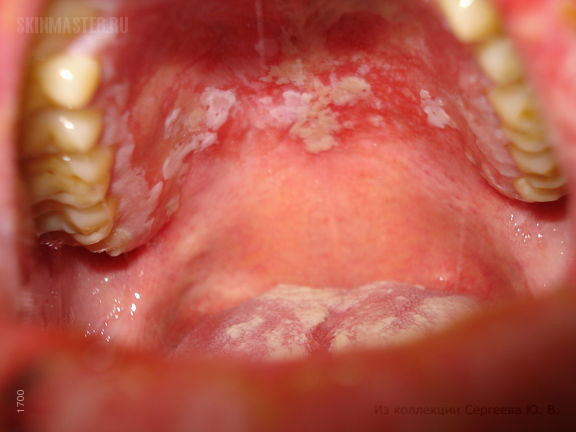

Красная сыпь обычно бывает признаком не слишком опасного вируса. Если же на ней есть белесоватый или какого-то другого оттенка налет, то это свидетельствует о наличии гноя. Он появляется при обширном спектре заболеваний:

Грибковая – это чаще всего молочница, которая бывает из-за плохой работы ЖКТ. Микрофлора нарушается, из-за этого может появиться сыпь. Обычно молочница появляется после приема антибиотиков или из-за снижения иммунитета. Сыпь в горле у ребенка бывает белесой. Врач в этом случае назначает антибактериальные лекарства, налаживающие работу ЖКТ. Пятна приобретают коричневый цвет, затем исчезают.